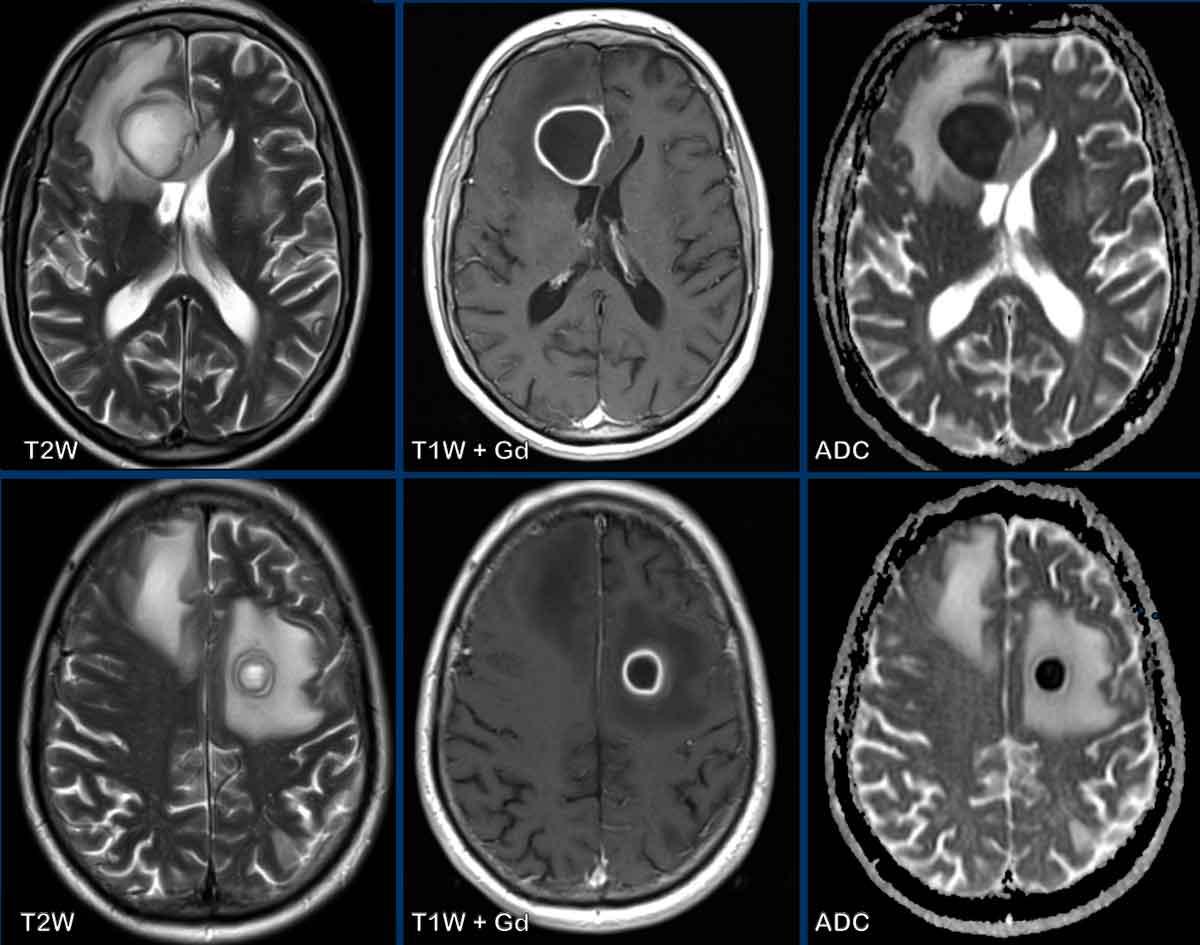

Các dấu hiệu MRI đặc trưng của áp-xe sinh mủ được trình bày trong bảng.

Dấu hiệu điển hình nhất là tổn thương ngấm thuốc ngoại vi với hạn chế khuếch tán ở trung tâm.

Các dấu hiệu bao gồm:

- Có hai tổn thương ngấm thuốc dạng vòng được bao quanh bởi phù não

- Trên chuỗi xung T2W, dấu hiệu viền đôi (double rim sign) hiện diện ở tổn thương thùy trán trái.

- Có hạn chế khuếch tán ở trung tâm.

- Có ngấm thuốc viền nhẵn.

Tất cả các dấu hiệu này phù hợp với chẩn đoán áp-xe não.

Dấu hiệu viền đôi trên chuỗi xung T2W có thể gặp trong tới 75% các trường hợp.

Điển hình là có ngấm thuốc viền hoàn toàn và hạn chế khuếch tán, nhưng đôi khi ngấm thuốc không hoàn toàn do ổ áp-xe hướng về phía não thất, chuẩn bị đổ mủ vào hệ thống não thất.

Có thể thấy sự khởi đầu của quá trình này ở ổ áp-xe thùy trán phải.

Khi ổ áp-xe này vỡ vào não thất, viền ngấm thuốc sẽ bị gián đoạn và sẽ xuất hiện hạn chế khuếch tán trong lòng não thất.